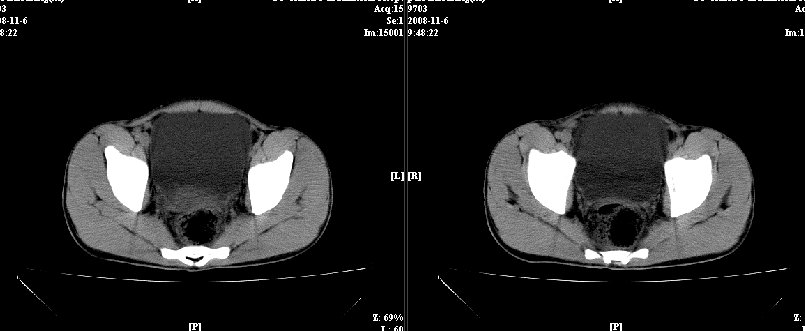

以下是引用dxm在2008-11-6 13:32:00的发言:[br]膀胱直肠窝积液 盲肠璧增厚 小肠淤积

以下是引用zsl6918在2008-11-6 14:13:00的发言:[br]如果阑尾炎病史明确,那腹腔及盆腔改变考虑脓肿形成.

以下是引用zjzjr在2008-11-6 14:37:00的发言:[br]支持阑尾炎伴盆腔及右髂窝脓肿形成